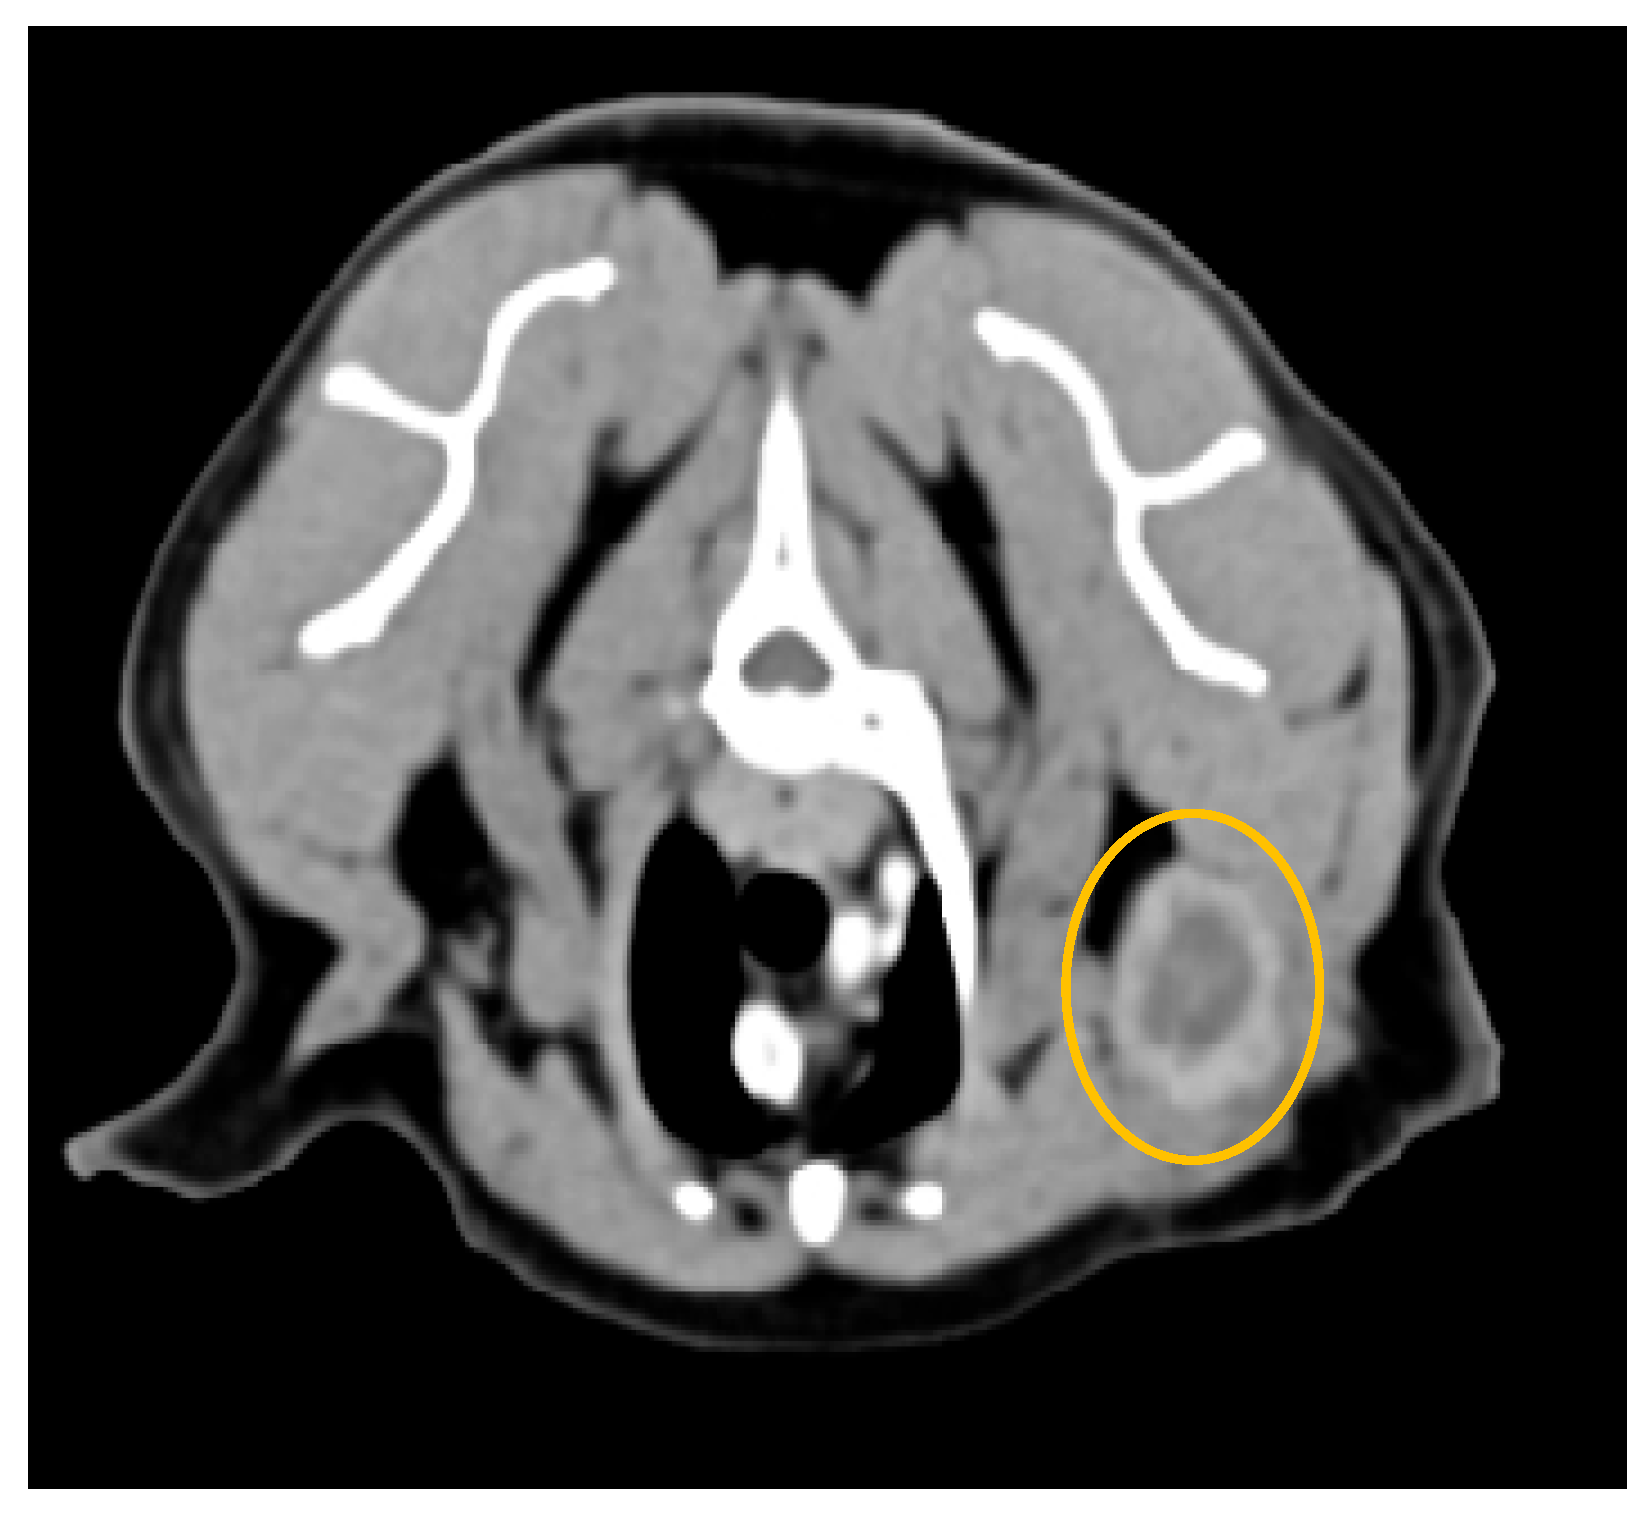

3.2. Computed Tomography

4.2. Computed Tomography